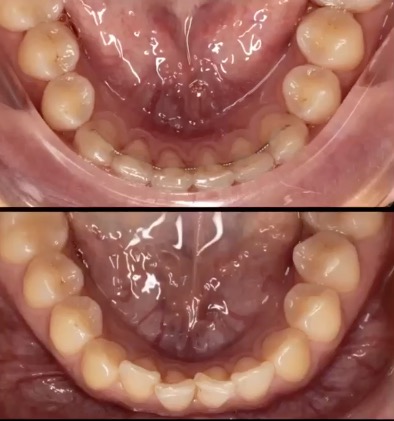

• La pianificazione 3D scanner guidata da parte dell’ortodontista dei micro-movimenti di ogni singolo dente che devono essere eseguiti al fine di ottenere l’occlusione perfetta.

• La progettazione di una o più serie di allineatori costituiti da materiali brevettati INVISALIGN in grado di trasferire forze in tempi ed intesità specifiche che il paziente dovrà cambiare seguendo le indicazioni dello specialista. In alcune situazioni verranno inseriti piccoli attacchi in resina, poi rimossi a fine trattamento, per aiutare gli allineatori ad eseguire anche i movimenti più difficili.